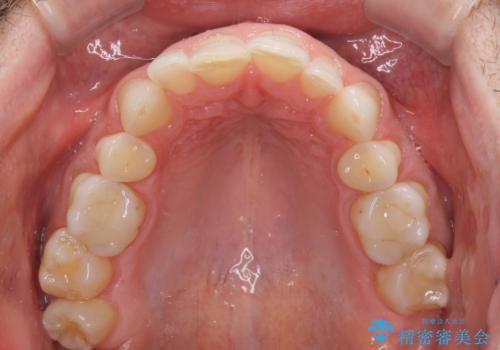

- 上下前歯の叢生を気にして来院された患者様です。

抜歯矯正をした後戻りということで、歯列不正はそれほど大きくなかったため、インビザライン・ライトを用いて矯正治療を行うこととしました。

前歯のデコボコが残っており、シミュレーション通りに動いていない部分がありましたが、再矯正であることやご本人の満足いくところまでデコボコが改善されたとのことで、治療を終了することとしました。